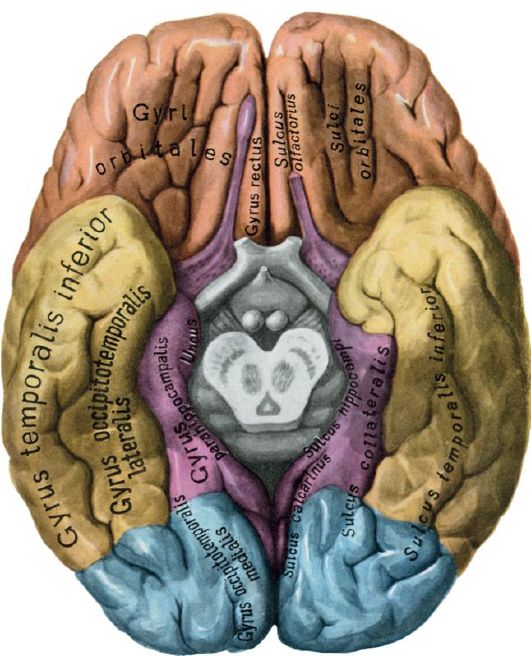

Анатомические снимки верхнелатеральной поверхности головного мозга